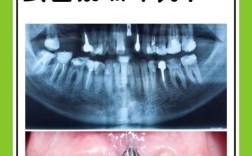

门牙两个拔掉 待种牙